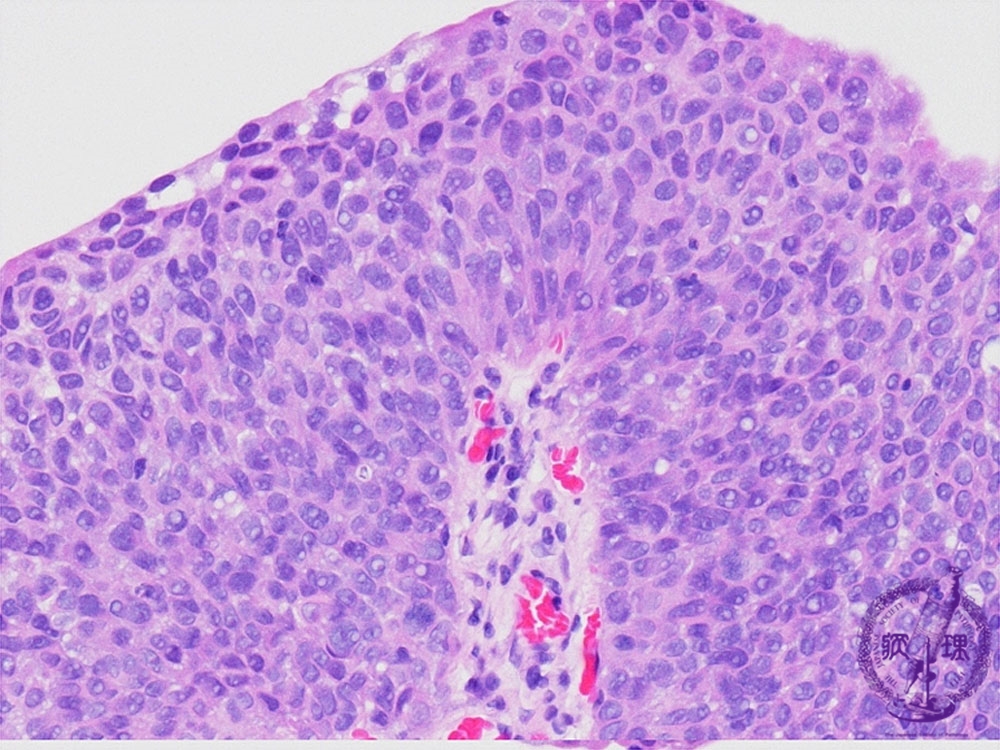

Microscopic findings (HE, high power view): G3, Cancer cells show a high cellularity with high nucleocytoplasmic ratio and hyperchromatism.